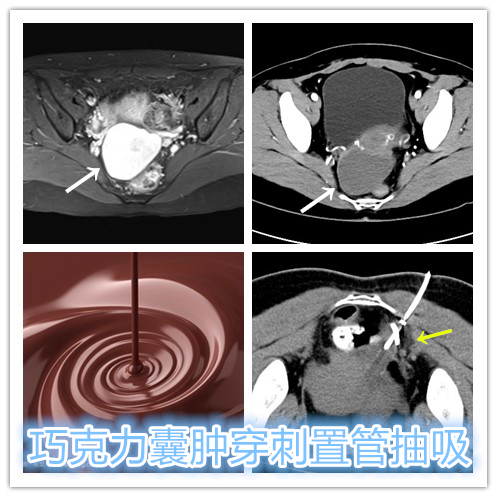

年轻女性,已生育,诊断为右侧卵巢巧克力囊肿。近1年经期不规律,伴有下腹闷胀不适,彩超监测发现右侧巧克力囊肿进行性增大。经药物保守调理治疗无缓解,因不愿接受妇科手术治疗,就诊要求行介入硬化治疗,遂行CT引导下巧克力囊肿穿刺置管抽吸+硬化治疗。

经留置引流管抽吸出浓稠积血,使用生理盐水反复冲洗直至囊液转为清亮,随后注入聚桂醇硬化剂保留腔内硬化破坏囊壁,2天后拔除引流管。术后3个月复查彩超显示囊肿已明显萎缩,月经恢复正常,经期已无明显不适。